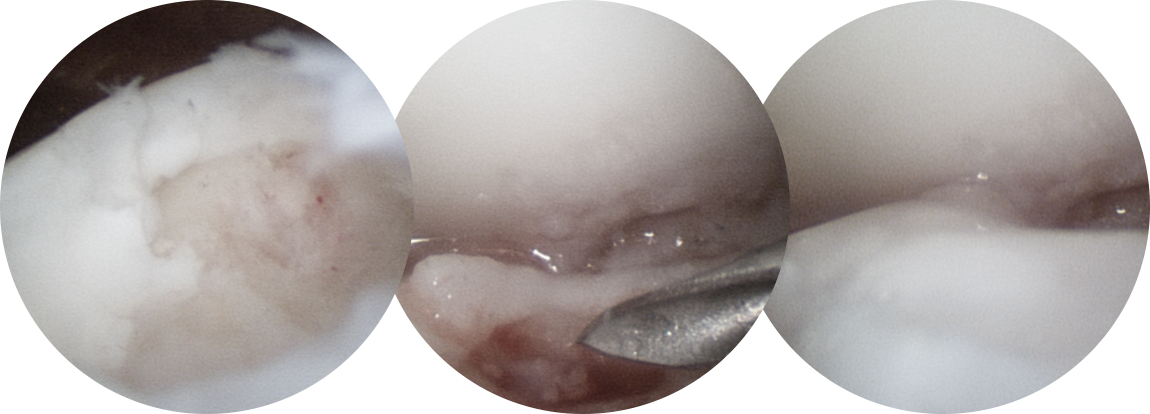

연골 손상이 있는 부위에 작은 구멍을 여러 개 내준 후, 골수에서부터 좋은 피가 잘 올라오는 것을 확인합니다.

연골 재생술을 같이 하는 것이 계획되었다면 콜라겐 혹은 줄기 세포로 결손부위를 도포해줍니다.

* 환자에게 받은 소중한 자료입니다.

거골의 내측부 연골 병변에 대해서 관절경을 통해 미세천공술과 콜라겐 주입술을 시행하였으며,

수술 5개월째 결손 부위에 연골이 잘 생성되어 있는 소견이 관찰되었습니다.